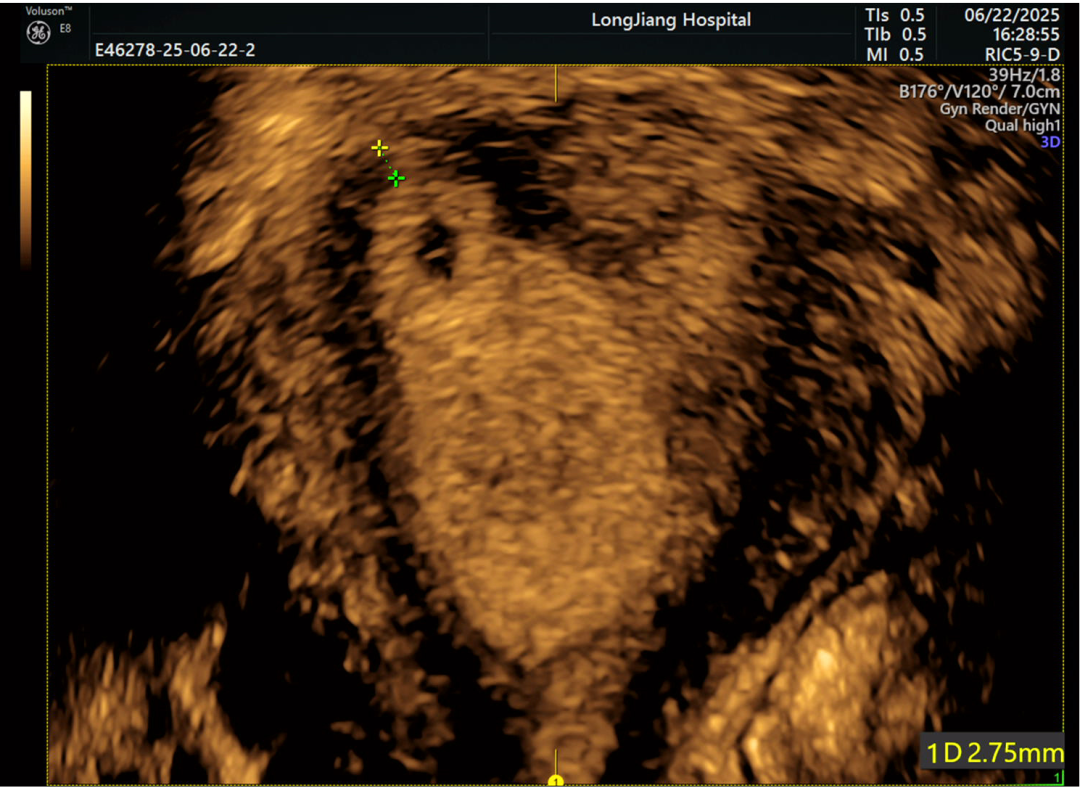

4. 复查“小宫殿”装修效果:如果之前做过宫腔镜手术(比如切息肉、分离粘连),用三维超声复查效果就超直观啦!

(节育环嵌顿)